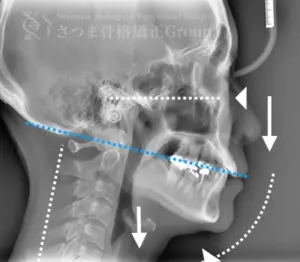

渋谷TMJ歯科クリニックでは、頭蓋および頸椎の歪みが顎位(あごの位置)と咬合(噛み合わせ)の乱れを引き起こし、その結果として顔の歪み、顎関節症、食いしばり、ストレートネックによる強い肩こり、さらには自律神経の乱れへとつながると考えています。

これらの問題を正確に評価するため、当院では セファロシステムによるレントゲン撮影(X-ray images) を行っています。

セファロ撮影によって 顎関節・頭蓋骨・頸椎の位置関係を客観的に可視化でき、施術前の状態を科学的に把握することが可能となります。

• 顎位のズレ

• 咬合の乱れ

• 頭位・頸椎姿勢のバランス

• 筋肉・関節の負担部位